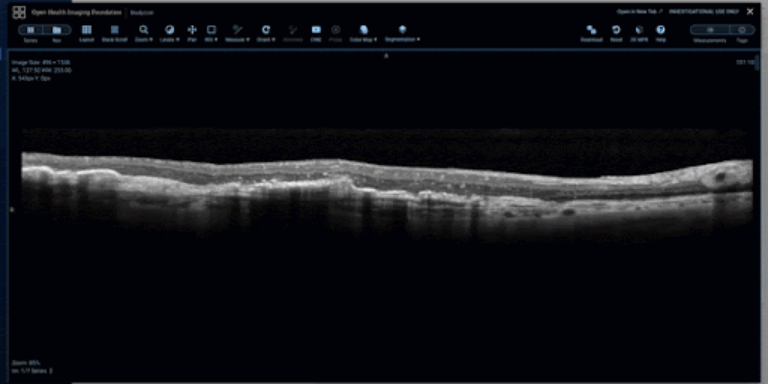

As shown below, the viewer supports an open freehand tool for retinal layer tracing, a closed freehand ROI tool for capturing distinct findings, such as intraretinal fluid pockets, and a sculpt tool for precise editing of freehand ROIs.

Open Freehand ROI tool for retinal layer tracing.